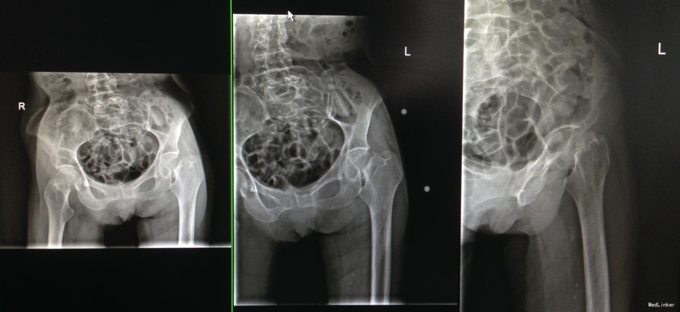

跌倒致左髋部疼痛不适伴活动受限3天 老年女性,家中跌倒后,左侧髋部疼痛。伴活动受限。于家中休养,疼痛不能缓解,翻身等活动后疼痛加重。遂来急诊就诊

查体:左侧下肢轻度外旋畸形。左下肢轴向叩击痛阳性。 辅检:左侧股骨颈骨折。

诊断:左侧股骨颈骨折 治疗:左侧人工股骨头置换